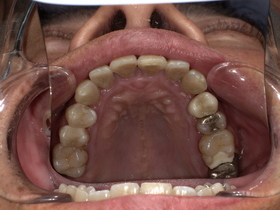

治療前の状態|詰め物の劣化と二次虫歯

診察の結果、以下の問題が確認されました。

■ 二次虫歯(再発虫歯)

詰め物と歯の隙間から細菌が侵入し、

👉 内部で虫歯が進行している状態

■ 適合不良(段差・隙間)

- 汚れが溜まりやすい

- 歯周病リスク増加

■ 噛み合わせの乱れ

欠けた状態を放置していたため、

👉 他の歯に負担がかかっていました

症例結果|Before / After

Before

- 詰め物が脱離

- 清潔感に欠ける状態